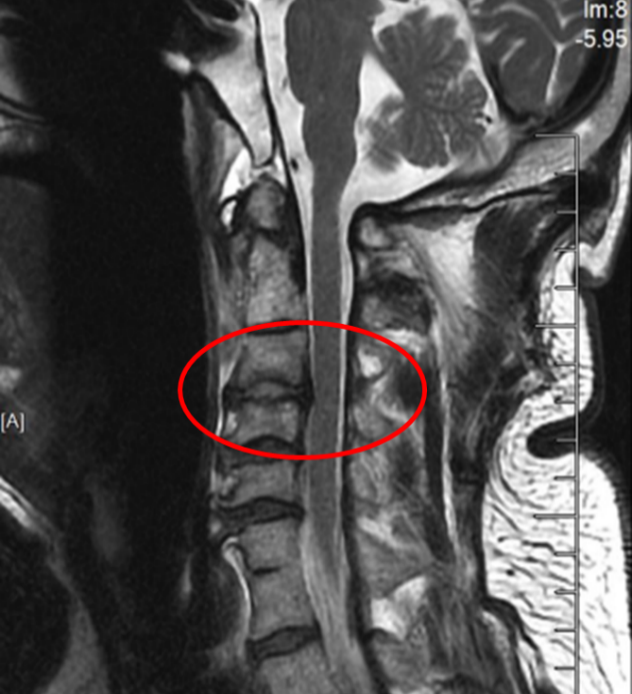

图3:骨科机器人

在麻醉手术科的严密监护下,刘义杰副主任医师首先熟练地完成了颈椎前路C3-4减压融合术(ACDF),成功解除了脊髓的压迫。然而,通过同一个仅3厘米的微小切口,精准地将螺钉植入游离且向后倾倒的齿状突具有极大的挑战性。关键时刻,骨科手术机器人发挥了“超级助手”的作用。团队利用机器人导航系统,对进钉点和角度进行了反复测算与调整,导针精准抵达目标。随后,由姜为民主任专利研发的一枚新型齿状突螺钉顺着通道顺利旋入,牢牢锁住了骨折端。整个过程出血量少,手术顺利完成。